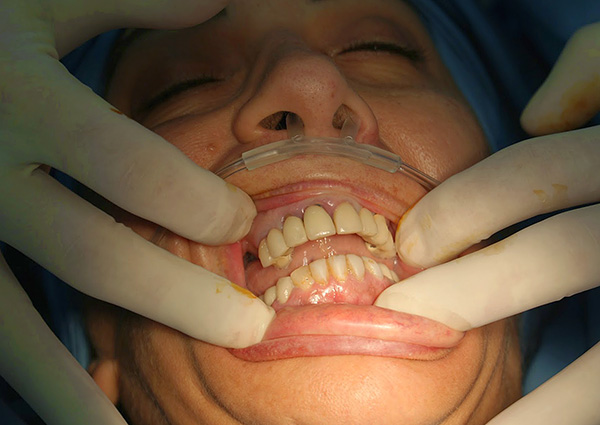

Se houver contra-indicações para anestesia local e (ou) indicações para anestesia, o implante é realizado com perda de consciência. A vantagem mais importante nesse caso é que, com essa operação, você pode garantir totalmente que, ao instalar implantes durante o sono, o paciente não sentirá dor ou emoções desagradáveis associadas ao tipo de instrumento dental (algumas pessoas sensíveis têm medo não apenas da dor, mas também o tipo de sangue, instrumentos e sons desagradáveis - perfuração, trituração etc.).

Na prática, este é o caso: a instalação de implantes dentários é mais frequentemente realizada sob anestesia local, quando uma pessoa está consciente desde o início até o final do procedimento e pode controlar direta ou indiretamente a situação. A anestesia, por outro lado, é uma boa alternativa nos casos em que a anestesia local não dá resultado ou pode até causar danos ao paciente durante a instalação de implantes dentários devido a contra-indicações.